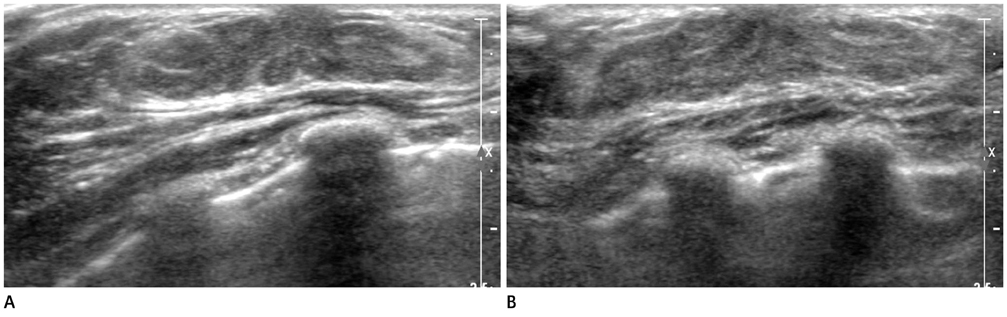

- The purpose of this study is to review various breast diseases in children and adolescents and to illustrate the sonographic findings. We reviewed the cases at our institution in order to identify breast disease in children and adolescent patients who underwent sonography and mammography. Breast disease in children and adolescents included developmental disturbance, infection, benign tumors and inherent defects. In contrast to adults, the radiologic findings of malignant breast conditions in pediatric populations have rarely been reported; however, we show ductal carcinoma in situ with juvenile fibroadenoma and rhabdomyosarcoma. During childhood and adolescence, the recognition and correct identification of physiologic breast development and specific lesions in breast entities on radiologic findings is most helpful in identifying and characterizing abnormalities and in guiding further investigation.